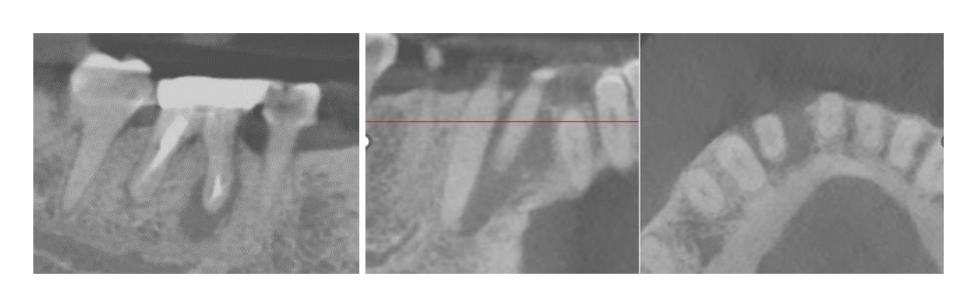

Figure 3. 3-D imaging of the lower right region disclosing magnitude of bony defect in bucco-lingual and occluso-gingival dimension in the area of #26, which could not be disclosed by 2-D imaging. In addition, failing endodontic treatment of tooth #30 is self-explanatory.